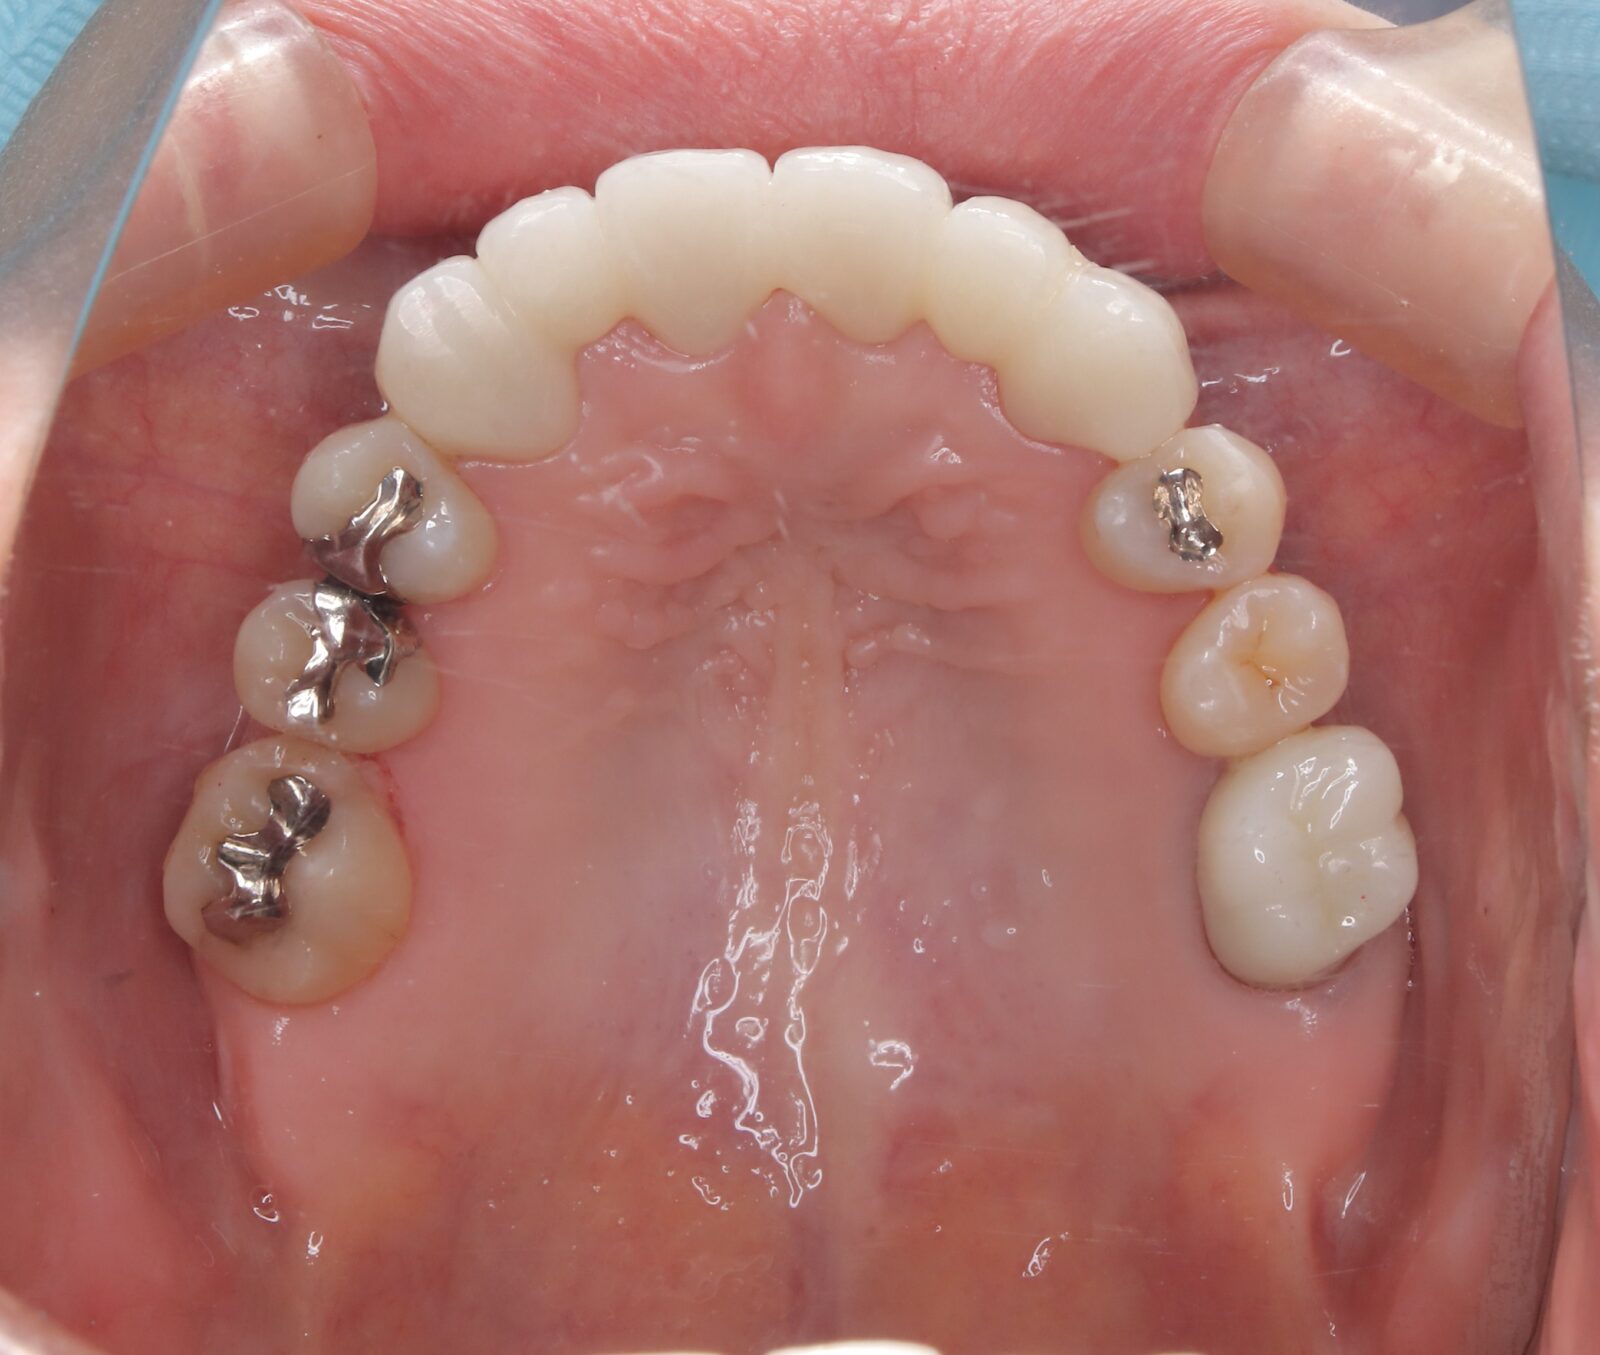

職業柄抜歯をすることができない患者様の症例

職業柄抜歯をすることができないため、小臼歯も親知らずも非抜歯の矯正となりました。 それでは歯を並べるためのスペースを確保できない。歯根の形状を分析し、可能な限り歯冠修復で前歯のサイズを小さくして、歯を動かすためのスペースを作り矯正をスタートした。 下顎前歯歯並びきれないこと、理想的な噛み合わせの獲得は難しいことをご理解いただき治療スタートした。 終了時に初期時の不自由がないことを確認済み。